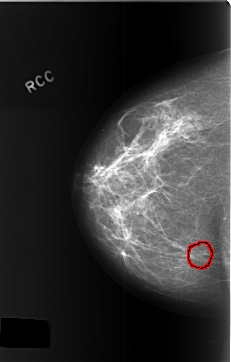

C_0381_1.RIGHT_MLO

FILE: C_0381_1.RIGHT_CC.OVERLAY

TOTAL_ABNORMALITIES 1

ABNORMALITY 1

LESION_TYPE CALCIFICATION TYPE AMORPHOUS DISTRIBUTION CLUSTERED

ASSESSMENT 4

SUBTLETY 5

PATHOLOGY BENIGN

TOTAL_OUTLINES 1

BOUNDARY